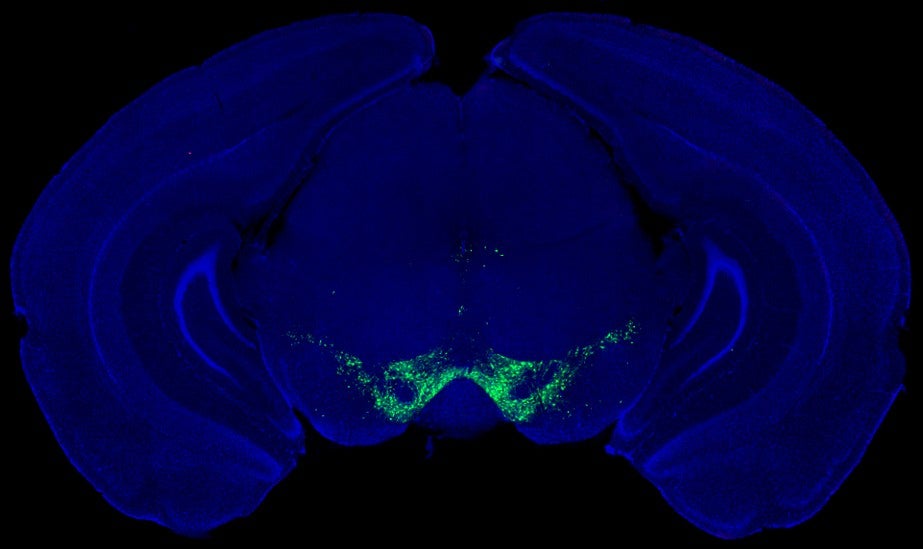

The next question was whether fast dopamine changes predicted how vigorous each movement would be. To find out, the team used a fluorescent dopamine sensor to track dopamine levels in the striatum while mice performed the task.

Water rewards triggered brief dopamine surges, as expected. But lever presses themselves were not tied to strong dopamine bursts. On average, dopamine levels dipped slightly when movement began and reached a low point near peak speed. Trial-by-trial analysis showed little or no link between dopamine levels at key moments and how fast or how far the lever moved.

The researchers repeated the measurements in another striatal region. Dopamine there often rose before movement and peaked near maximum speed. Even so, movement vigor still showed no strong relationship to these brief signals. The findings suggested that subsecond dopamine fluctuations do not encode the vigor of individual actions.